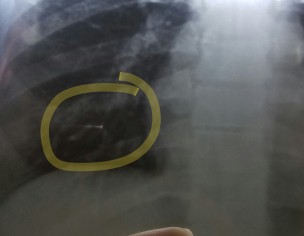

Is this shadow in my chest xray something to worry about? The doctor I consulted said that it is an xray defect though I do feel pain in the right side of my chest.

It’s foreign body particle probably. Plz repeat XRay and check pulmonologist.